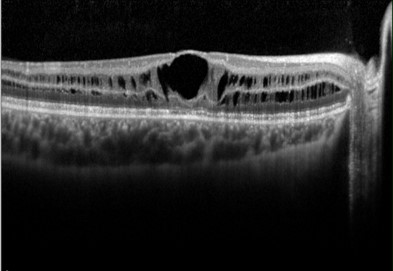

The characteristic sign of X-linked retinoschisis is a spoke-wheel appearance radiating from the fovea with OCT showing splitting of the neurosensory retina at multiple retinal layers creating schisis cavities. Peripheral retinoschisis is reported in 50-70% of the cases and can lead to complications such as retinal detachment and vitreous haemorrhage.

More infoSpectralis OCT macular line scans (right and left eye)

More infoSpectralis OCT line scans through an area of inferior retinoschisis